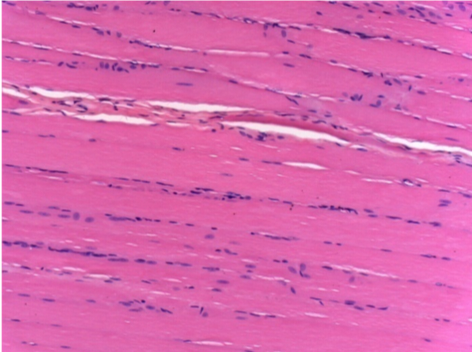

Л: Претибіальний м'яз - без лікування